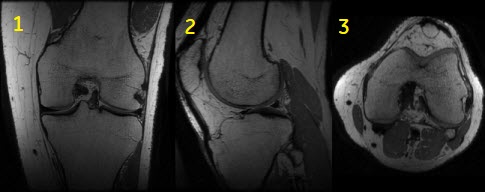

Cube and Cube T2 FLAIR scan

Cube and Cube T2 FLAIR have a unique acquisition and reconstruction technique that allows for high resolution imaging in all three dimensions with the goal of acquiring isotropic voxels (all voxel dimensions, height, width, and depth, are equal). The advantage of acquiring isotropic voxels is that the data can be acquired in the plane that yields the greatest efficiency and then reformatted into any plane thus reducing the exam time. Images may be reformatted with slightly thicker slices (e.g., 3 mm) in order to improve SNR and reduce the number of images to be reviewed.

Use Cube to acquire high resolution imaging in all three dimensions with the goal of acquiring isotropic voxels (all voxel dimensions, height, width, and depth, are equal).

| Number | Description |

|---|---|

| 1 | Acquired coronal image |

| 2 | Reformatted sagittal image |

| 3 | Reformatted axial image |